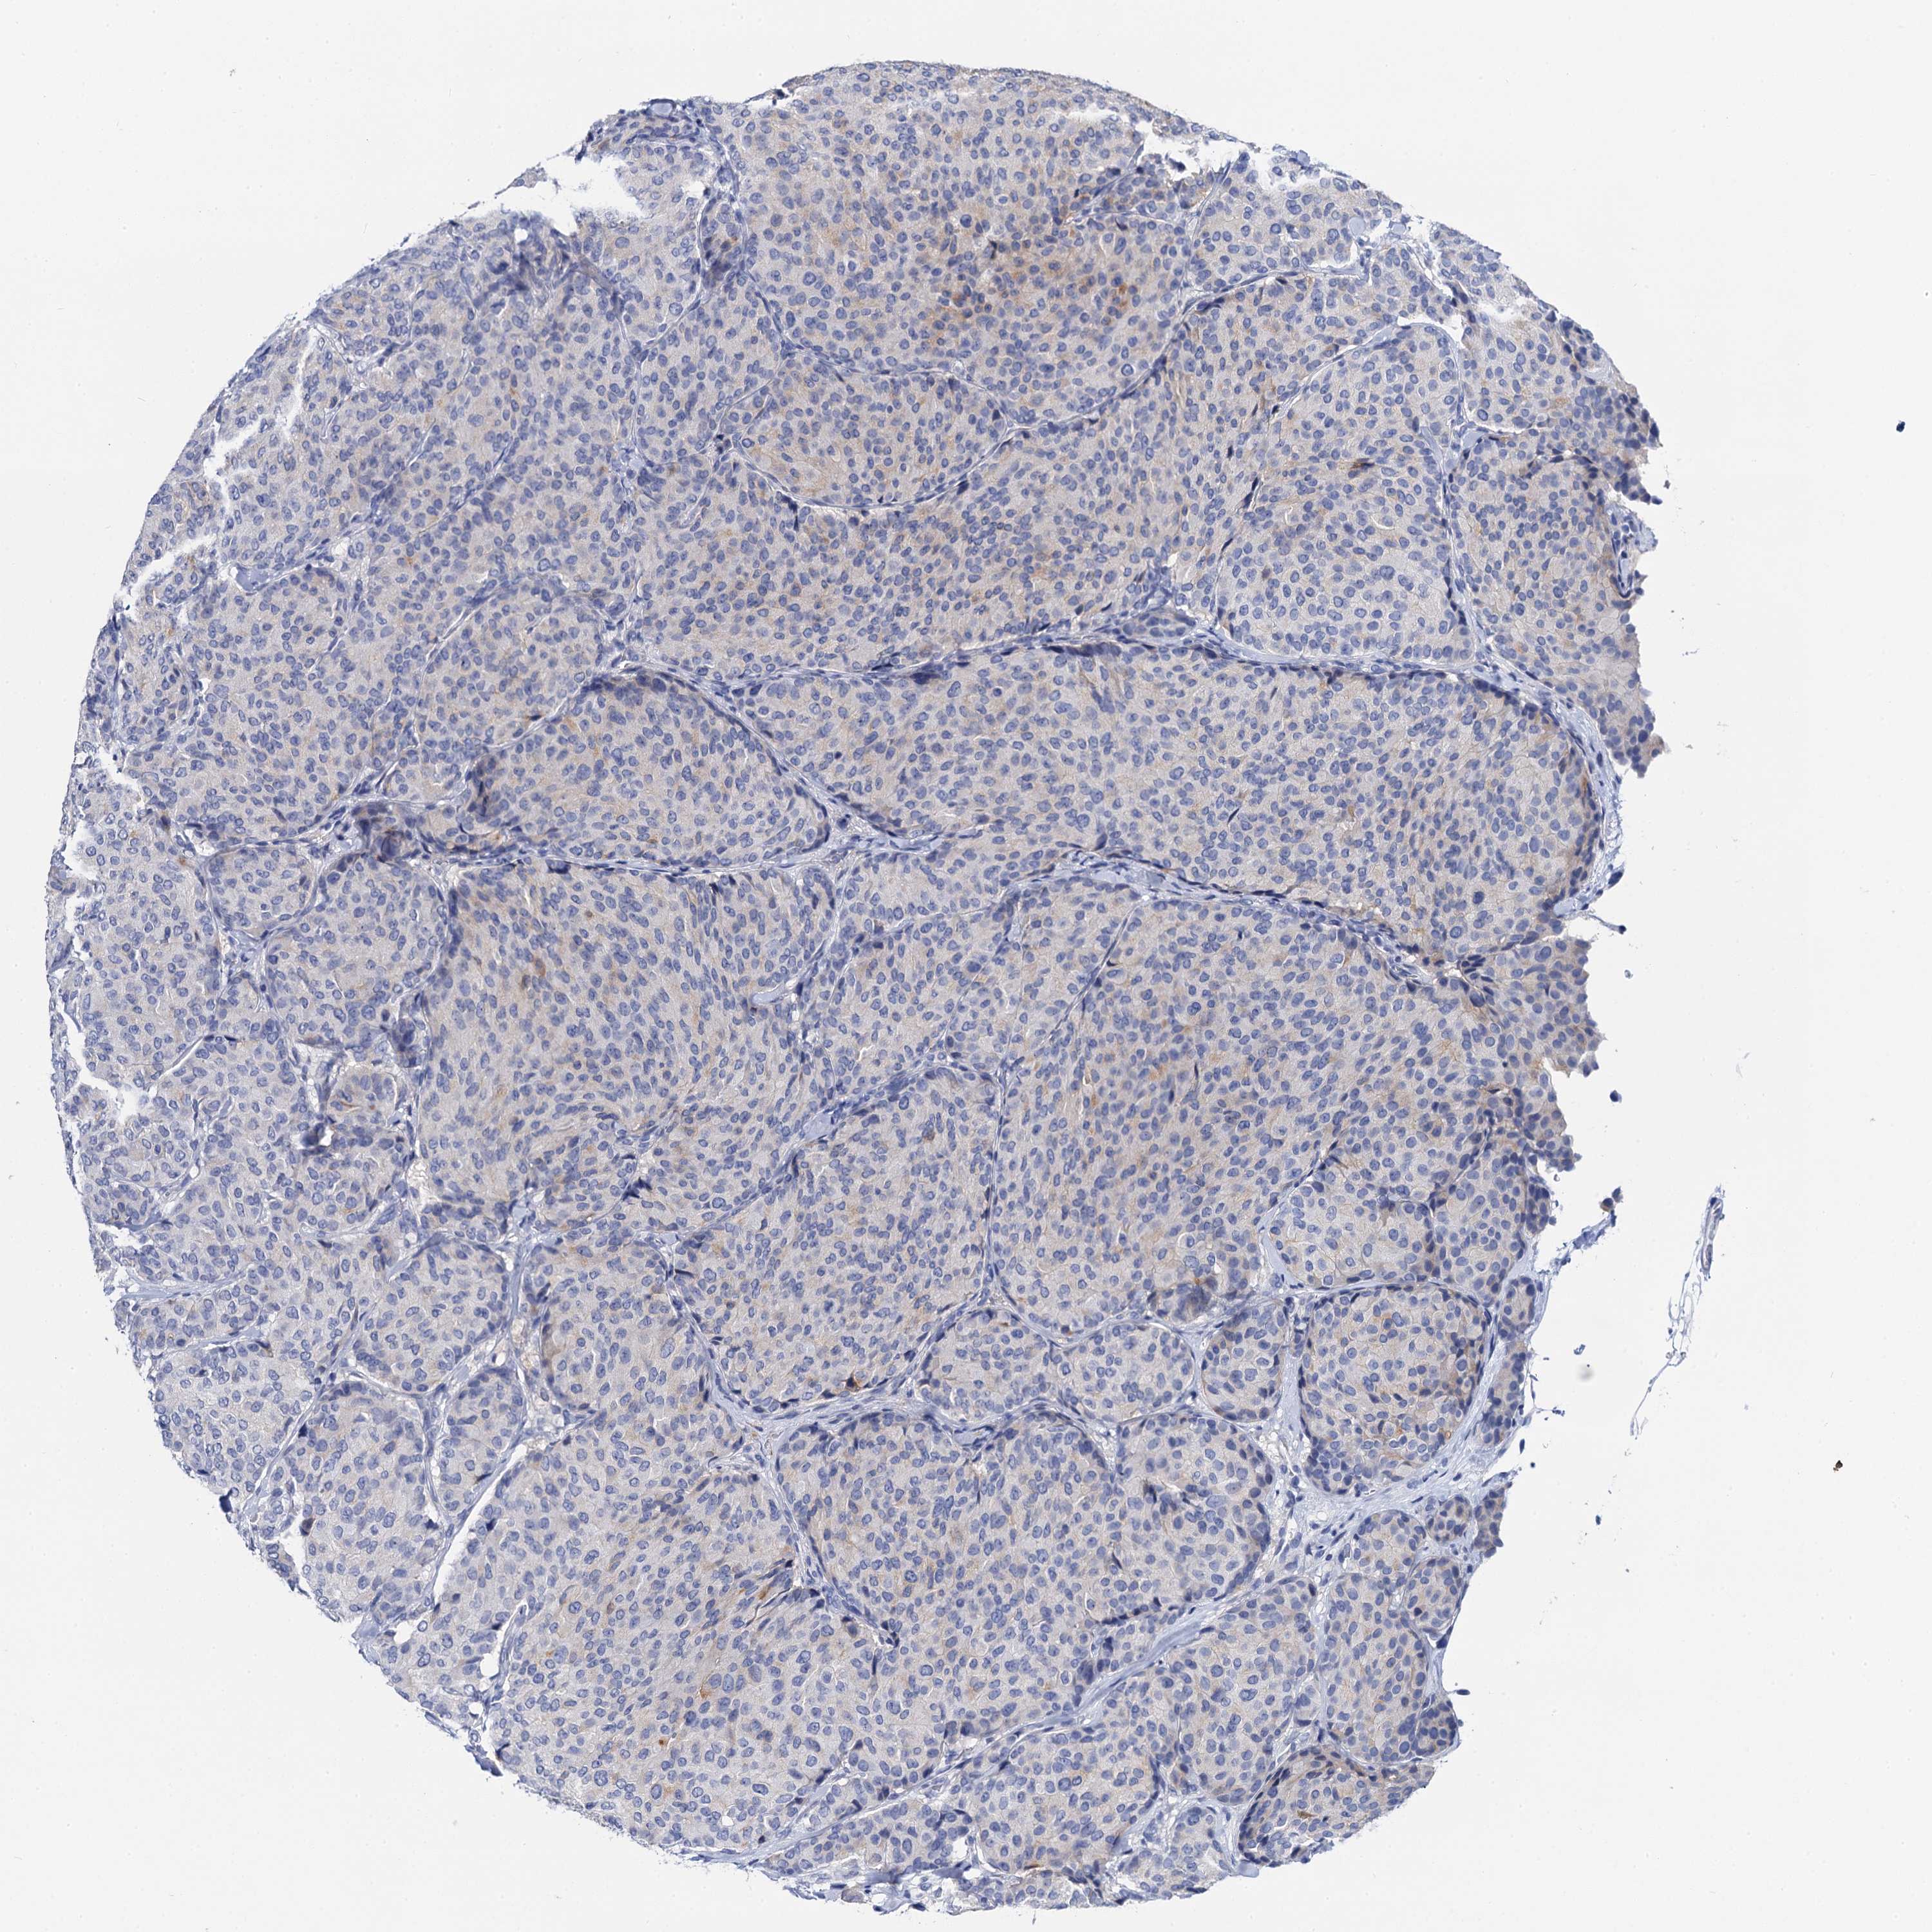

BRCA TCGA BRCA VALIDATION PROTEIN EXPRESSION